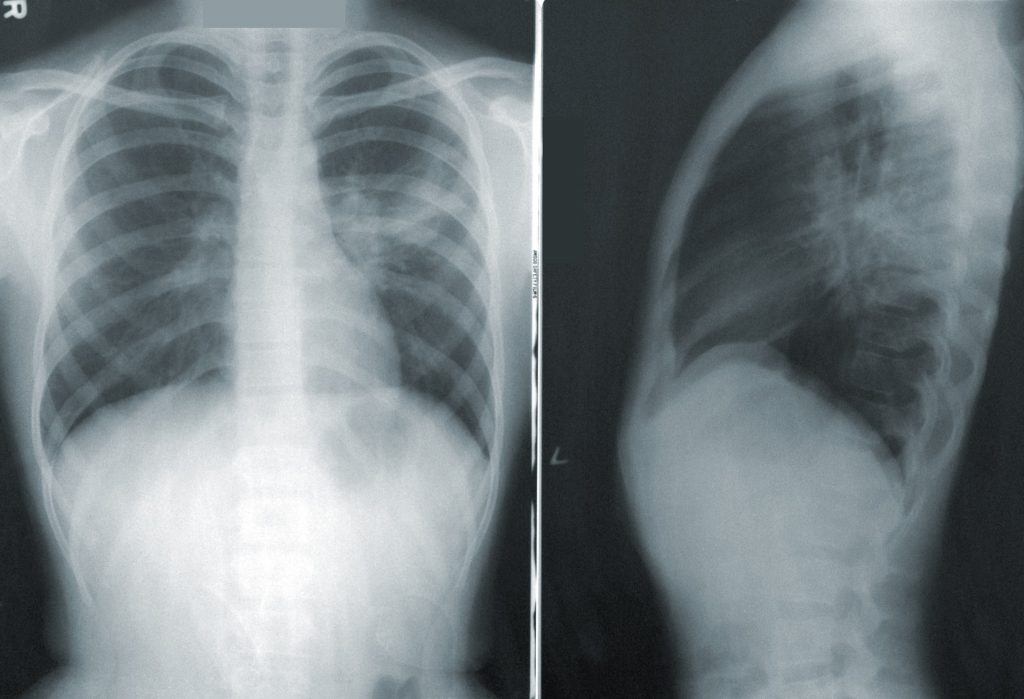

Toraxia puede identificar y caracterizar los signos patológicos sugestivos del coronavirus en las radiografías de tórax mediante el uso de inteligencia artificial.

En ambas versiones, se logra disminuir el error de diagnóstico radiológico que puede llegar a un 50% para médicos generales, debido a la baja formación en el análisis de radiografía de tórax, siendo así una herramienta para salvar vidas, ya que entrega su opinión sobre los signos patológicos encontrados, destacando con colores el nivel de magnitud y la localización de los patrones de diferentes enfermedades, solo en segundos.